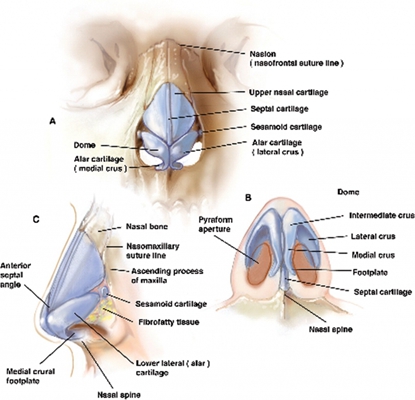

鼻中隔偏曲圖片

鼻中隔彎曲手術圖解 (7)

鼻中隔彎曲手術圖解 (8)

鼻中隔彎曲手術圖解 (9)